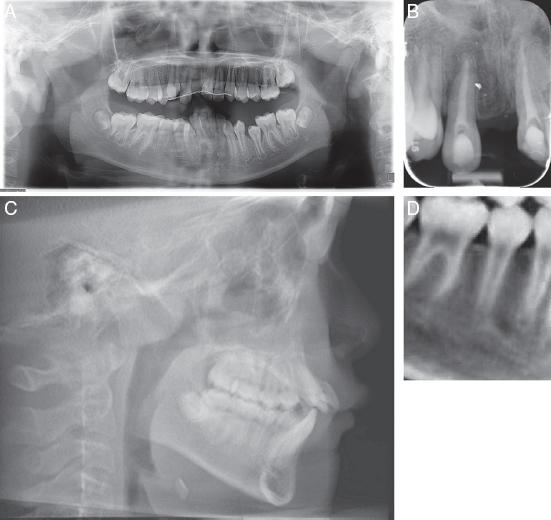

Figure 1.